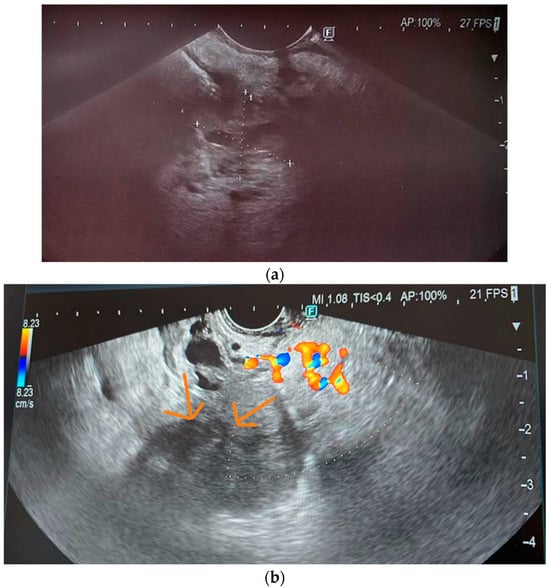

3.5. Endoscopic Ultrasound

10.4. Endoscopic Ultrasound